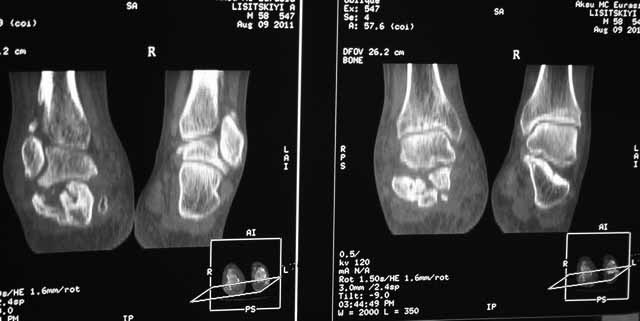

КТ перелома пяточной кости

возможно выполнение подтаранного артродеза.Но после производства КТ в августе появились

сомнения в консолидации перелома.Ранее у нас не было опыта КТ переломов стопы и сканы привели

в замешательство.Прилагаю снимки со дня поступления, августовские пациентом не

представлены.С благодарностью примем советы коллег.